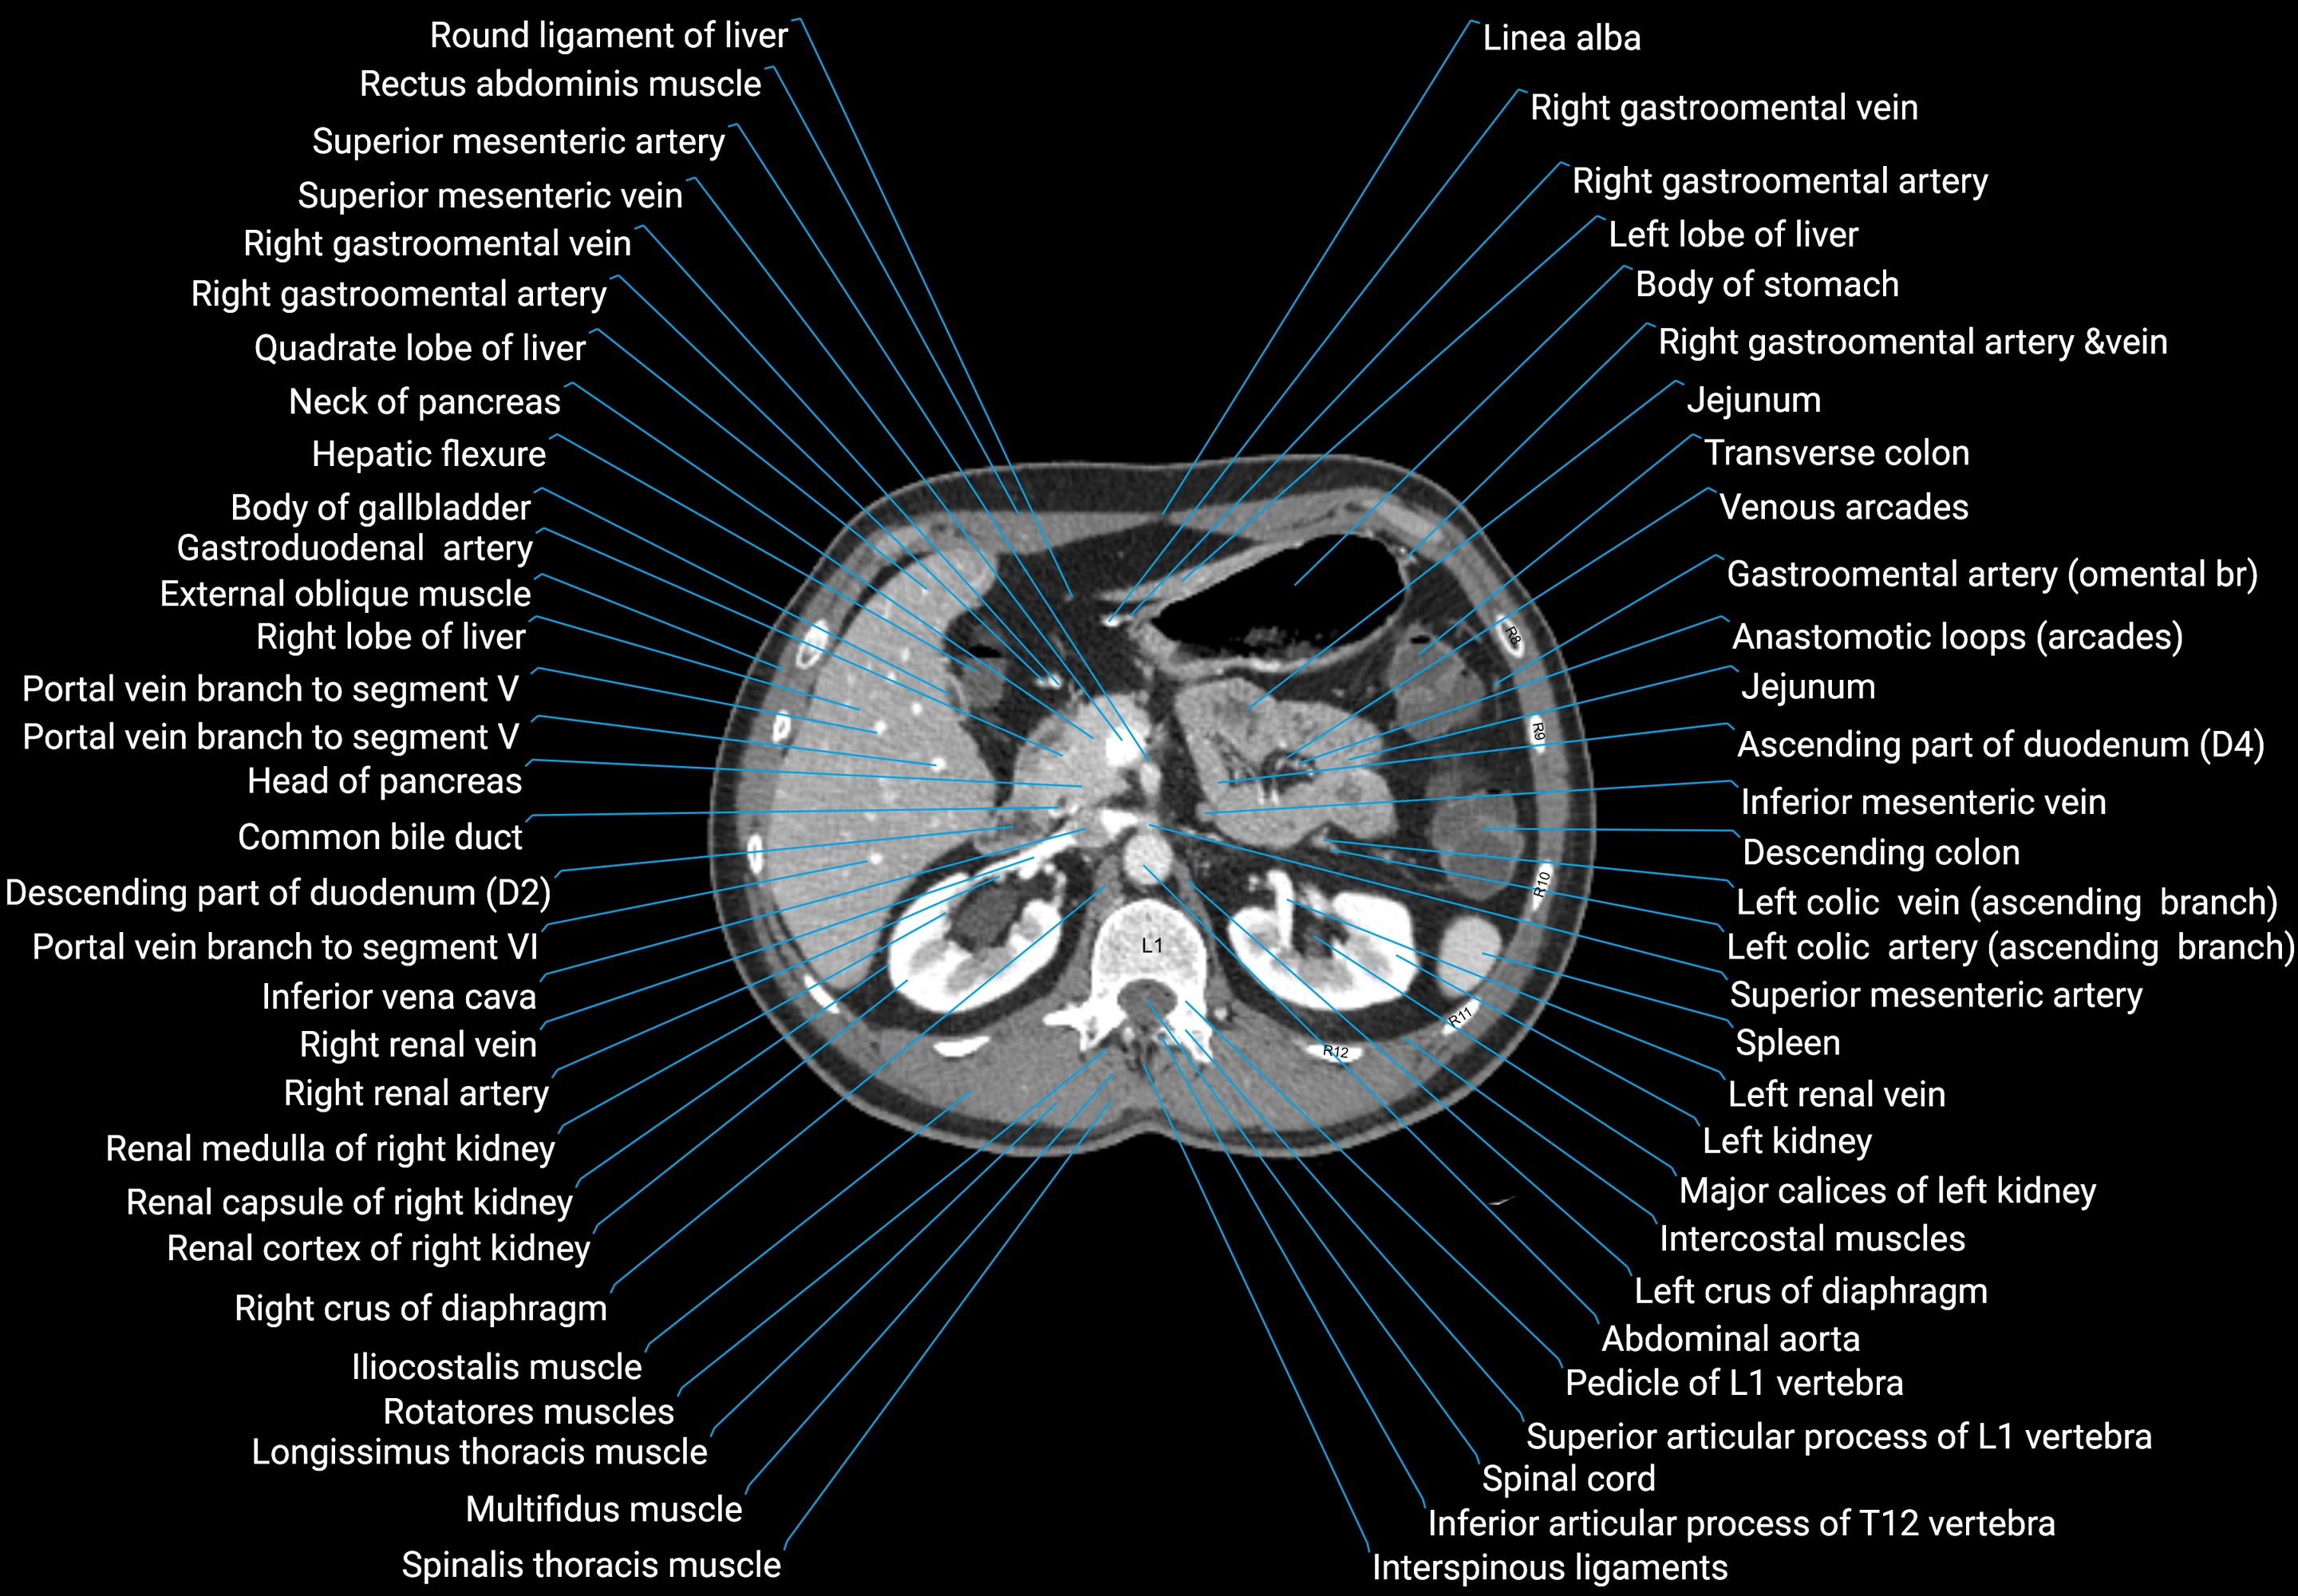

CT images